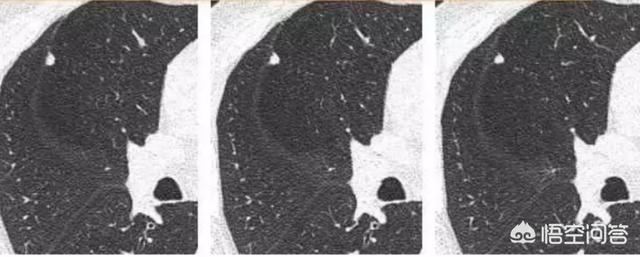

Un petit nodule solide comme celui-ci, d'environ 4 mm, était lisse et ne présentait aucun signe évident de malignité. Mais deux ans et quatre mois plus tard :

La pathologie a ensuite confirmé qu'il s'agissait d'un cancer du poumon à petites cellules.